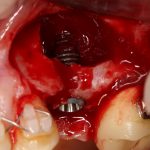

Глянем на то, что получилось:

Осталось адаптировать костный блок (убрать острые края), проверить его фиксацию и, при необходимости, добавить винты. Десятисекундное дело.

Изоляция области аутографта и имплантатов барьерной мембраной.

Перекрывать костный блок барьерной мембраной или оставить так? По этому вопросу есть много мнений. Между тем, в публикации по методике есть ясное показание, когда это требуется.

Конкретно в этом клиническом случае между костным аутотрансплантатом, ложем и имплантатами есть пустое пространство. Если его не изолировать от мягких тканей, они прорастут и осложнят интеграцию аутографта. Поэтому я решил перекрыть костный блок барьерной мембраной, пусть это делает хирургическую операцию немного дороже.

На этом этапе есть несколько нюансов, о которых я хочу рассказать отдельно.

— я использовал барьерную мембрану Geistlich Bio-Gide, которая имеет две разные поверхности: с одной стороны она рыхлая «адгезивная», с другой — гладкая и прочная. Как укладывать — на результат не влияет, но в плане удобства рыхлую поверхность мы «приклеиваем» к тому, на чем требуется барьерную мембрану удержать. В данном случае хотелось бы удержать её на костной поверхности — следовательно, мы укладываем её рыхлой поверхностью к кости.

Ремарка: примечательно, что во время синуслифтинга ситуация иная - там требуется удержать барьерную мембрану на слизистой оболочке верхнечелюстной пазухи. Следовательно, рыхлая поверхность - на стороне шнайдеровой мембраны.

— много лет мы используем антибиотики для интраоперационной профилактики инфекционно-воспалительных осложнений. Уже в то время мы пришли к выводу, что удобнее всего — порошки антибактериальных препаратов для приготовления раствором: дешевые, стерильные, в удобной упаковке. Прямо в виде порошка их можно добавлять в графт, растворы для ирригации, либо использовать так, как показано на фото. Еще мы используем порошок антибиотика для изготовления пасты, которой обрабатываем имплантаты в процессе ревизии или при лечении периимплантита. Это удобнее и эффективнее, чем интраоперационное использование жидких форм антибактериальных препаратов.

— ты знаешь, что барьерная мембрана может выполнять две функции, каркасную и изолирующую. Первая функция требует обязательной фиксации и натяжения, вторая — нет. В нашем случае «каркасом» регенерата является костный блок, а барьерная мембрана нужна только для изоляции. Поэтому она не требует натяжения и фиксации пинами.

После я внимательно проверил, что костный блок и имплантаты полностью перекрыты. Теперь рану можно ушивать.